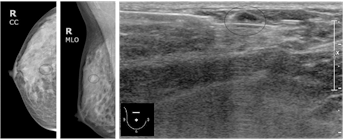

Ä¡¹ÐÀ¯¹æÀ» °®´Â ¿©¼º¿¡¼ Ãß°¡ÀûÀÎ ÃÊÀ½ÆÄ°¡ ÇÊ¿äÇÒ ¼ö ÀÖ°í, ¿µ»ó°Ë»ç¿¡¼ ¹ß°ßµÈ Á¾±«¸¦ ÃÊÀ½ÆÄ¸¦ ÀÌ¿ëÇÏ¿© ¼¼Ä§ÈíÀÎ »ý°Ë ¼¼Æ÷°Ë»ç³ª ħ»ý°Ë Á¶Á÷°Ë»ç¸¦ ÇÒ ¼ö ÀÖ½À´Ï´Ù.

Áõ·Ê - À¯°ü³» ¾ÏÁ¾ : ¼®È¸È º´º¯À» µ¿¹ÝÇÏÁö ¾Ê´Â À¯°ü³» ¾ÏÁ¾ (ħ»ý°Ë)

Áõ·Ê - ¼öÁú¾Ï : ¾ç¼ºÁ¾¾ç°ú Èí»çÇÑ ¼Ò°ß(ħ»ý°Ë)

Áõ·Ê - ´Ù¹ß¼º À¯¹æ¾Ï (¼¼Ä§ÈíÀÎ »ý°Ë)